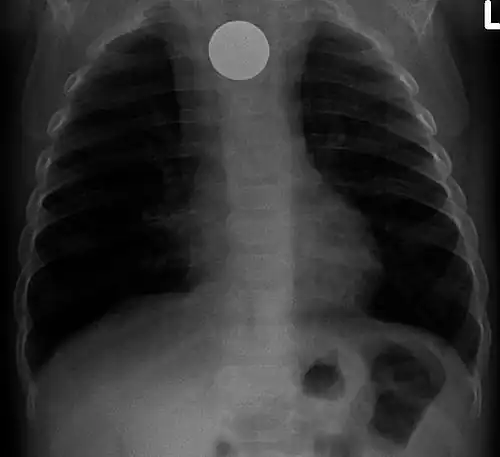

One of the most common locations for a foreign body is the alimentary tract.

It is possible for foreign bodies to enter the tract from the mouth or rectum.

Both children and adults experience problems caused by foreign objects becoming lodged within their bodies. Young children, in particular, are naturally curious and may intentionally put shiny objects, such as coins or button batteries, into their mouths. They also like to insert objects into their ear canals and nostrils.[1] The severity of a foreign body can range from unconcerning to a life-threatening emergency. For example, a coin causes local pressure on the tissue but generally is not a medical emergency to remove. A button battery, which can be a very similar size to a coin, generates hydroxide ions at the anode and causes a chemical burn in two hours.[2] An ingested button battery that is stuck in the esophagus is a medical emergency. In 2009, Avolio Luigi and Martucciello Giuseppe showed that although ingested nonmagnetic foreign bodies are likely to be passed spontaneously without consequence, ingested magnets (magnetic toys) may attract each other through children's intestinal walls and cause severe damage, such as pressure necrosis, perforation, intestinal fistulas, volvulus, and obstruction.[3]